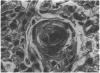

Images in this article